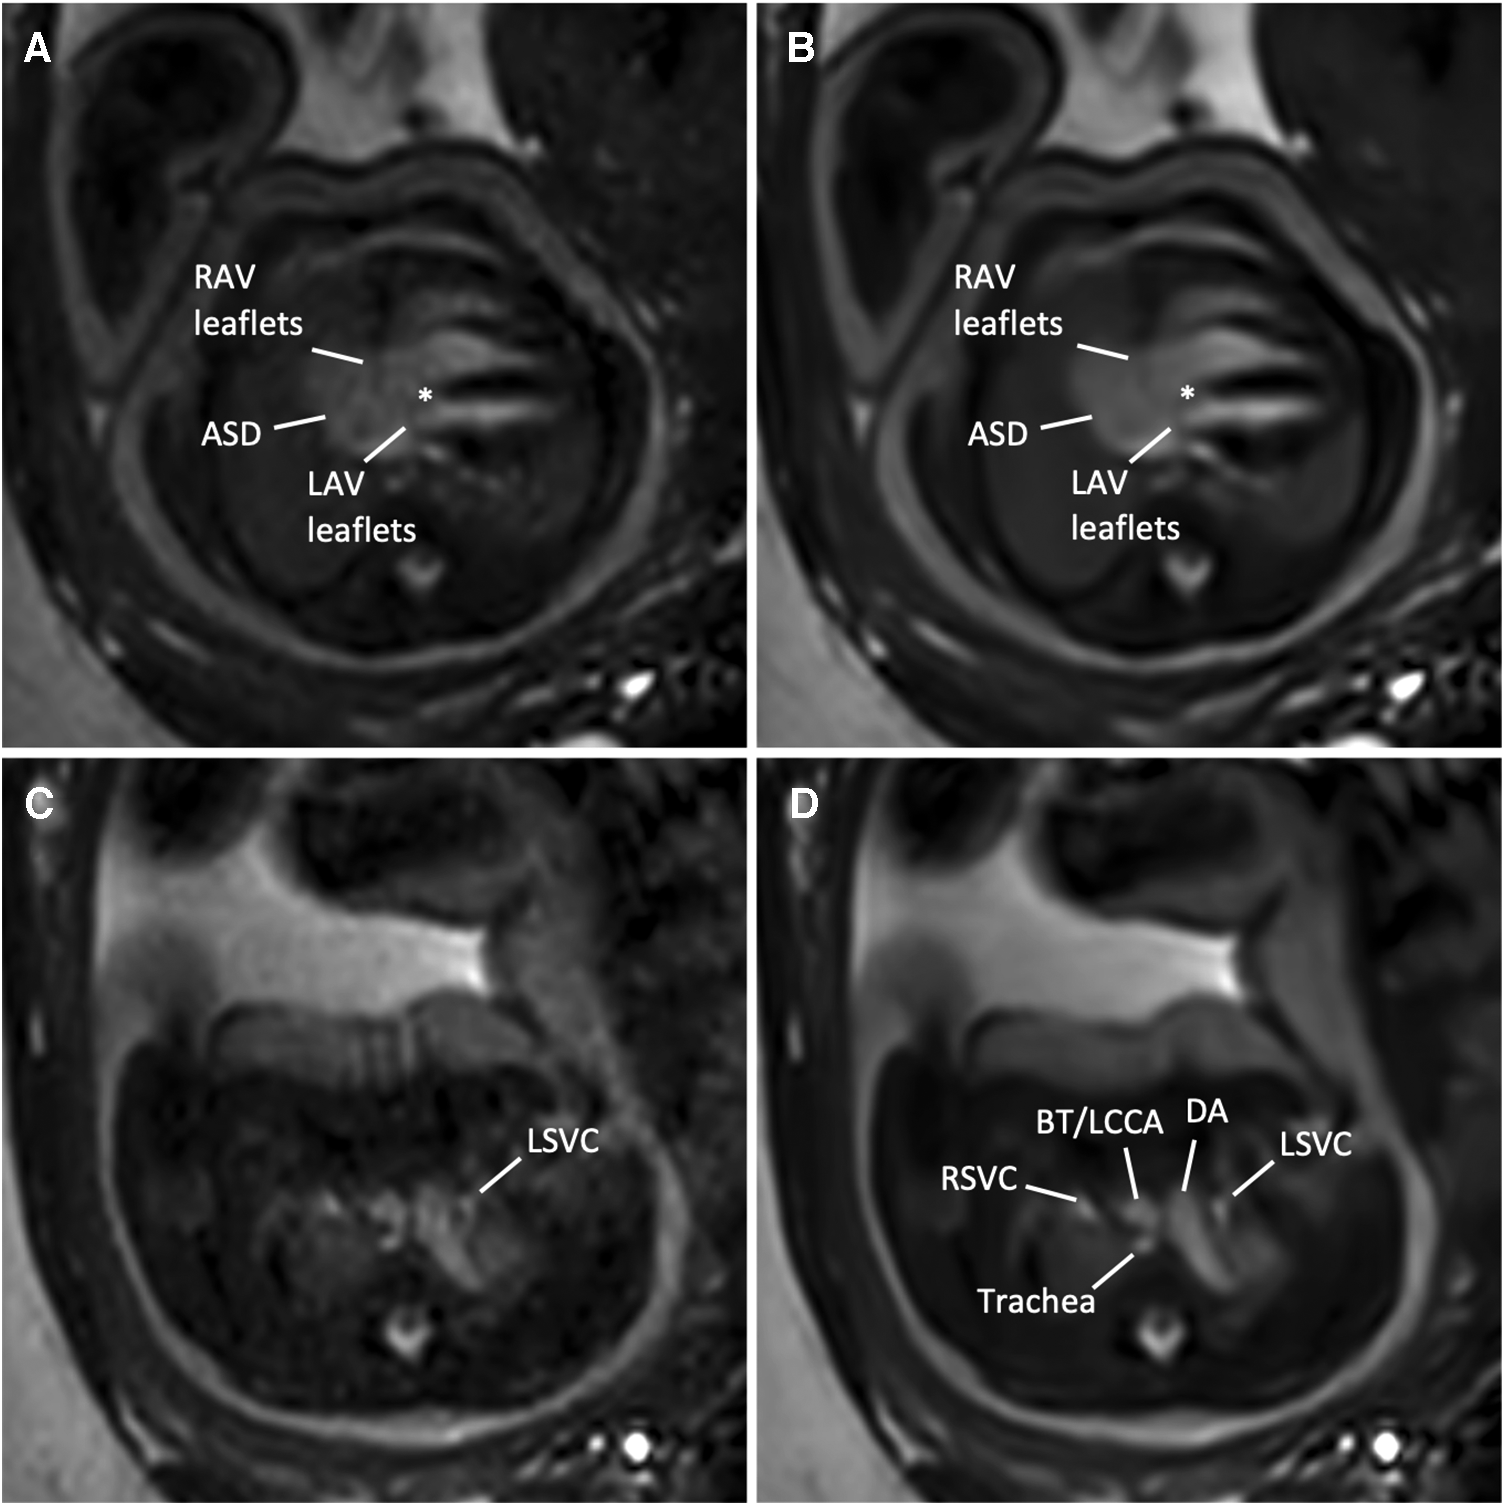

Confidence in diagnostic reading was rated higher when the bSSFP DL cine images were used to assess different cardiovascular structures (see Figure 4 and Table 4). Image examples demonstrating higher diagnostic confidence of bSSFP DL images for evaluation of the atrioventricular valves in a fetus with an intermediate-type atrioventricular septal defect and evaluation of the double aortic arch in another fetus are provided in Figures 5, 6.

Figure 6

(A,C) Standard CS and corresponding (B,D) DL image reconstructions of an axial balanced steady-state free precession cine sequence in a 35-year-old woman at a gestational age of 36 weeks and 3 days with an intermediate atrioventricular (AV) septal defect of the fetus. Images at AV level (A,B) revealed a large (type I and II) atrial septal defect (ASD), right AV and left AV leaflets, and a small defect in the basal portion of the interventricular septum (asterisk), indicating an intermediate-type AV canal. Note the clear delineation of the AV leaflets in the DL denoised image (B) compared with the standard CS reconstructed image (A) In addition, MRI revealed a left persistent superior vena cava (LSVC, C,D), draining into the coronary sinus (not shown). Adjacent structures at this level are the right superior vena cava, the ductus arteriosus, the supra-aortic vessels, including the brachiocephalic trunk (BT) and the left common carotid artery (LCCA), and the trachea. Both standard CS (Supplementary Movie S3) and DL-reconstructed cine images at the AV level (Supplementary Movie S4) are also provided. DA, ductus arteriosus; LAV, left atrioventricular valve orifice; RAV, right atrioventricular valve; RSVC, right superior vena cava.